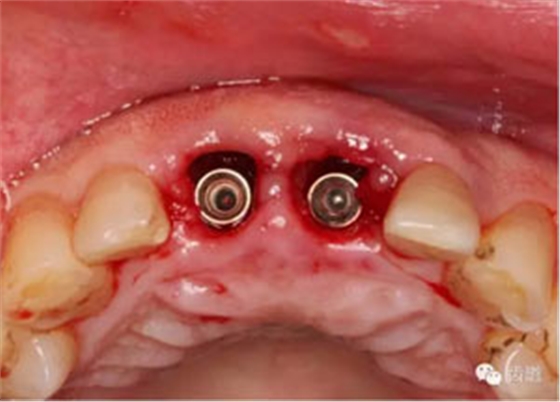

植入種植體(唇側(cè)留2-3mm jumping gap)

確定植入深度(齦下3-4mm)

小直徑愈合基臺(tái)就位后唇側(cè)植骨

更換大直徑愈合基臺(tái)